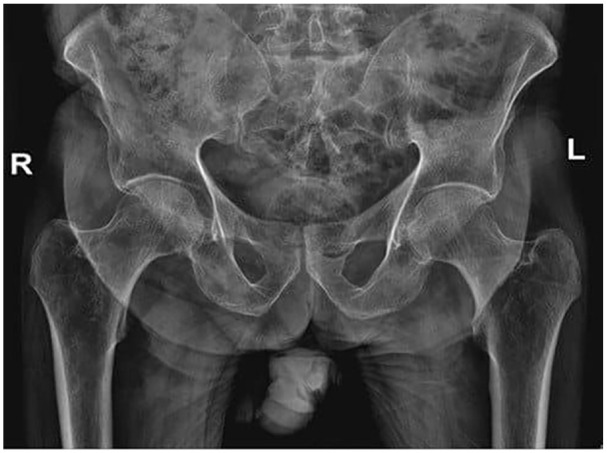

Diabetes mellitus is associated with an increased risk of osteoporosis and fractures due to impaired bone metabolism and increased fall risk. This case report highlights a 49-year-old Palestinian man with long-standing poorly controlled type 2 diabetes who presented with progressive back pain following a hypoglycemic syncopal episode. Clinical assessment and imaging, including magnetic resonance imaging (MRI) and Dual-Energy X-ray Absorptiometry (DEXA), confirmed a vertebral compression fracture at D12-L1 and severe osteoporosis. Laboratory investigations ruled out secondary causes of osteoporosis. The patient was treated with zoledronic acid, pain management, and improved glycemic control, leading to symptom relief and better metabolic outcomes after 6 months. This case underscores the importance of early osteoporosis screening in diabetic patients and highlights the need for an integrated approach to managing both diabetes and bone health to prevent fractures in high-risk individuals.